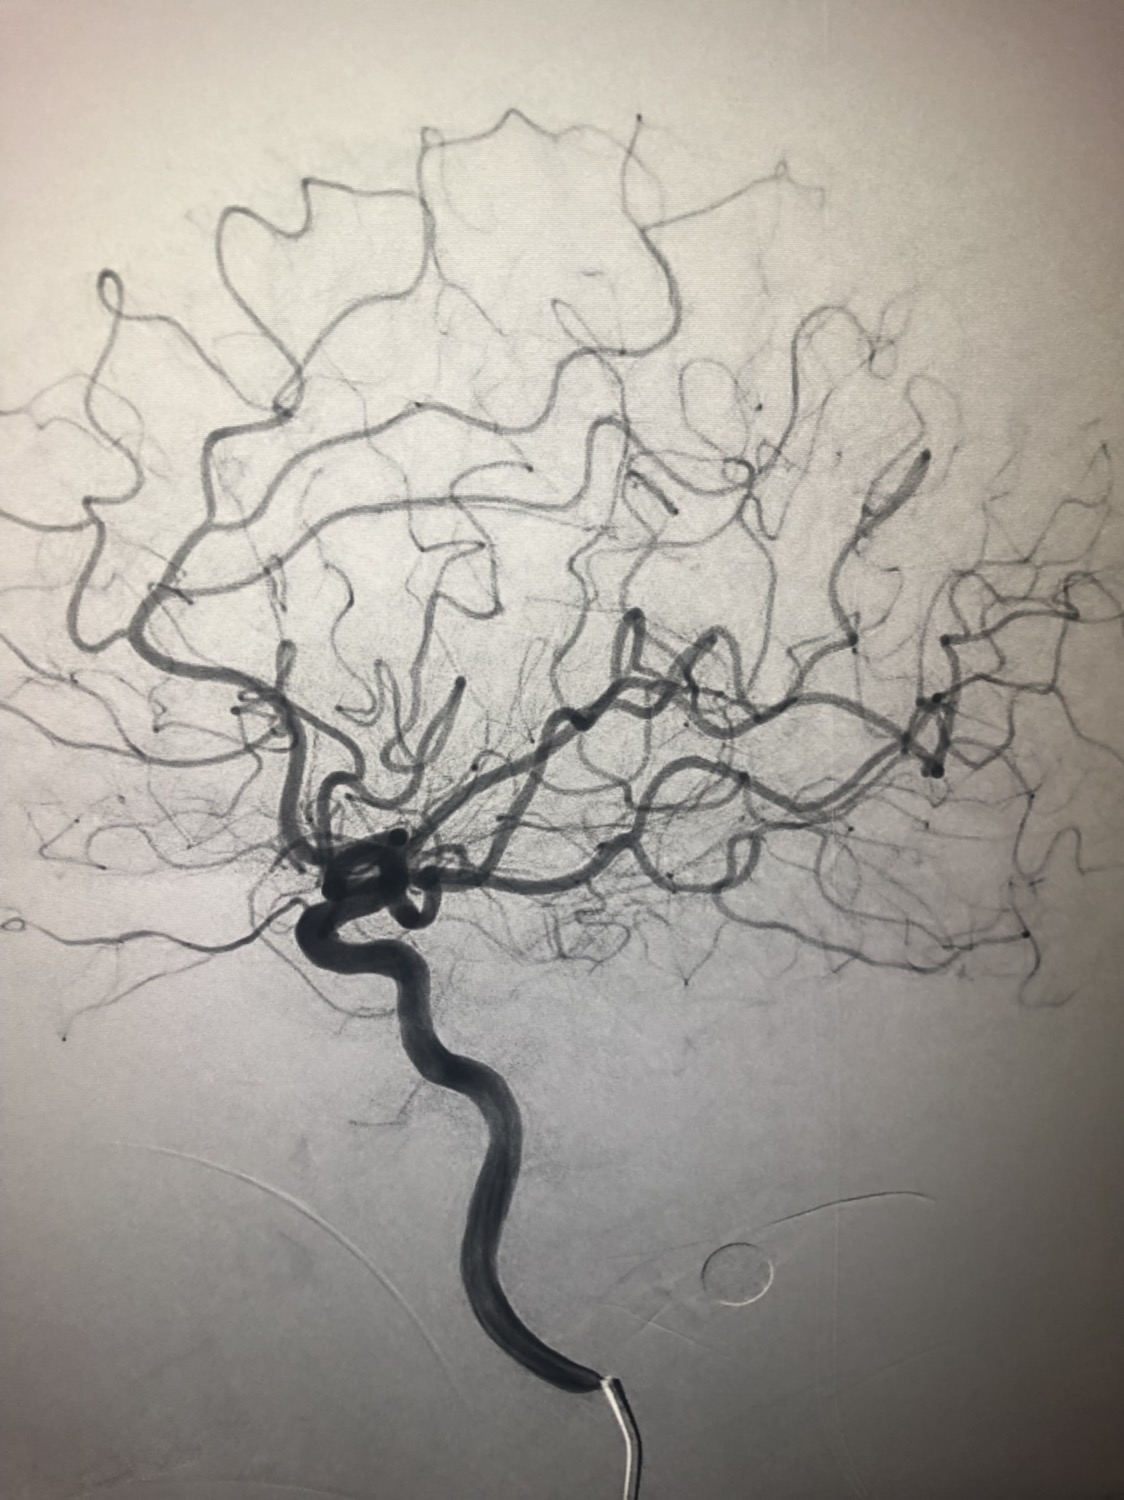

1周前房颤栓塞肱动脉,切开取栓后服用利伐沙班3天。突发偏瘫凝视3小时。上台看M3、A3血栓,国产普威森6f125cm抽吸导管高到位结合尼科3x20mm小支架,结合精细操作,m3和a3的血栓也可以轻松取出。不刺激血管。加造影射线16min两次取栓两个血管再通。

柔软的国产普威森微导管,高到位。

3x20mm的国产reco支架,适合分支血管取栓。

术后良好。